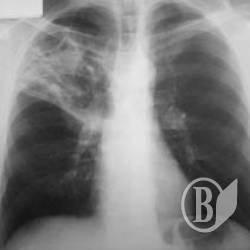

Майже 30% туберкульозу легень виявляється вже при розпаді легеневої тканини.